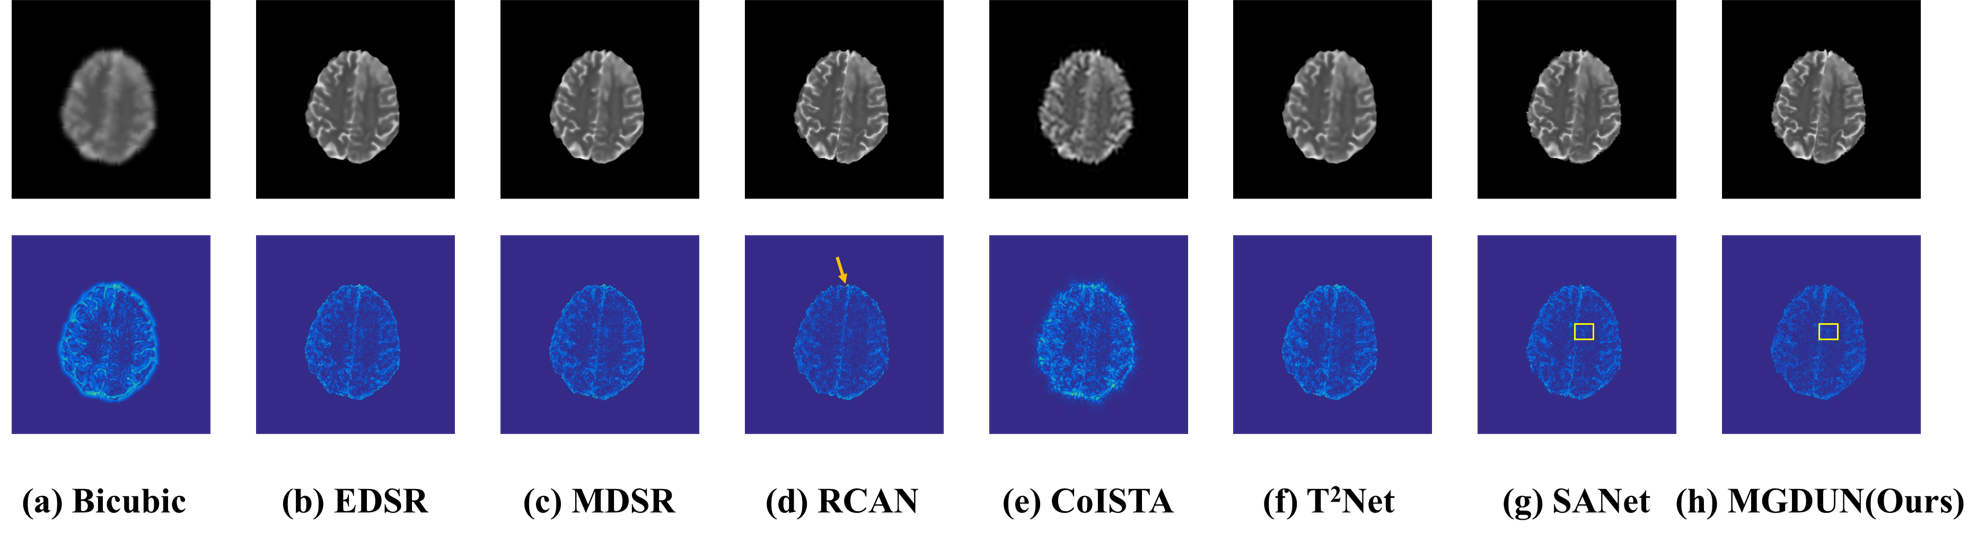

4.3.2. Qualitative results

We provide qualitative comparison results on the IXI dataset as well as the BraTs dataset and their corresponding error maps in Fig. 3 and Fig. 4. The texture of error maps represents the restoration error, the smoother the texture, the better the reconstruction. As we can see, the input has significant aliasing artifacts and lacks anatomical details. It can be noted that our model recovers the image with fewer visible artifacts and reconstructs more details than other competing methods. The quality improvement achieved by MDCUN may be associated with the full usage of the feature maps from the former stages to refine the final results.